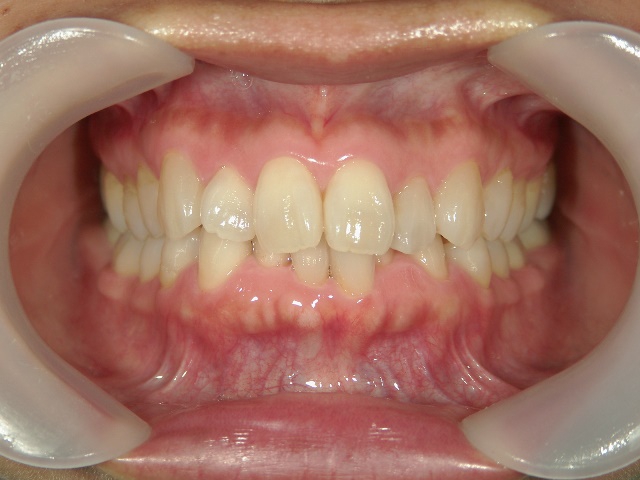

矯正歯科 治療後矯正歯科 プチワイヤー矯正 治療後矯正歯科(プチワイヤー矯正)治療後

矯正歯科 治療後 ミニインプラントを2本埋入し、下顎前歯を圧下